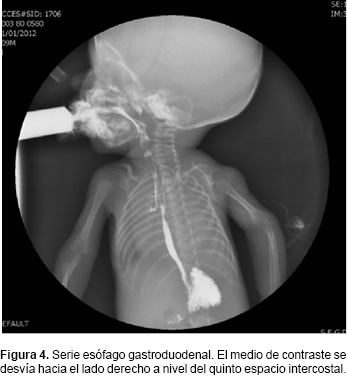

Al reingreso presentó succión débil, por lo que se realizó gastrostomía para mejorar la nutrición y, a través de una serie esofagogastroduodenal, se identificó el paso del medio de contraste a vía aérea (Figura 4), diagnosticándose la presencia de fístula traqueoesofágica en ''H'' (Figura 5).